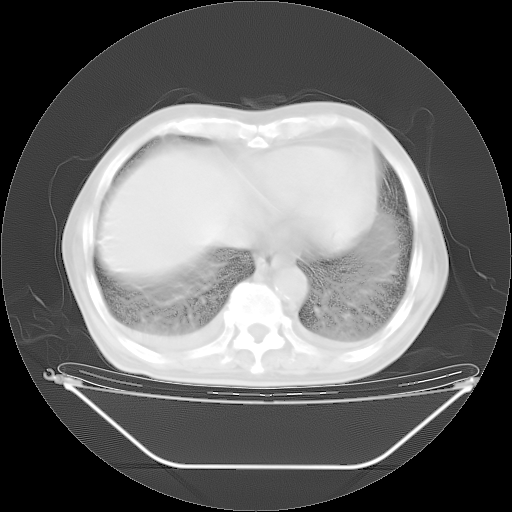

今天复查肺部CT,发现双肺广泛磨玻璃样改变。所以我把3月19日和5月9日相隔50天的肺部CT上传。请大家会诊。

5月9日肺部CT(在4月27日齐鲁医院肺部CT描述部分肺组织磨玻璃样改变,12天后肺组织广泛磨玻璃样改变)

大致读了系列胸部CT:纵隔窗无明显异常,肺窗:从4、27至今:主要是双肺中下野外带可见毛玻璃样改变,目前处于急性肺泡炎阶段,至于原因考虑1、结替组织或胶原血管性疾病所致?2、恶性疾病如恶组在肺部所致的表现或细支气管肺泡癌?3、药物或其它原因如肺蛋白沉着症所致肺泡炎目前不太可能?总之,明天就去请我院的呼吸科、感染科、血液科和临免专家会诊哈。